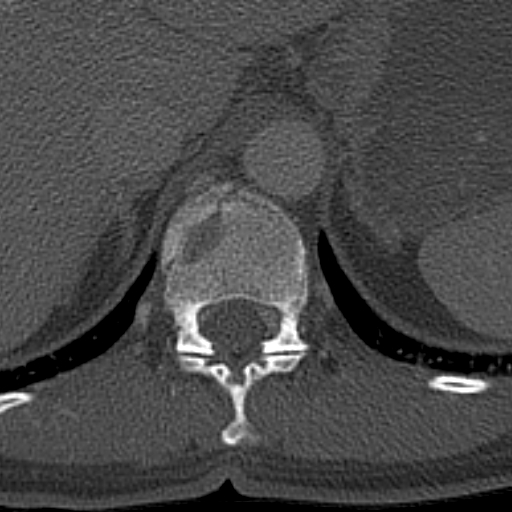

15.2.2.1. In spine trauma

Conventional X-ray exmination is still the primary imaging modality in cases of smaller traumas where clinical symptoms suggest that the damage is mostly affecting the paravertebral soft tissues. In the setting of polytrauma, checking for spinal injuries on the CT scan is part of the image evalutaion.

During evaluation the cervical spine needs to be examined the most urgently which allows us to decide whether the cervical collar is safe to be removed or if it is safe to intubate the patient using the regular method of hyperextension of the neck (e.g. when preparing for urgent surgery). We need to pay extra attention to the possible dissection of the vertebral arteries as they are running between bony structures!

When examining the spine, it is important to decide that the injury is stable or unstable. AO classification of fractures should be used avoid miscommunication. This includes the evaluation of the intervertebral discs and the ligaments which are better appreciated with an MR study and provide extra information for surgical planning. MR studies are also necessary in cases where the CT scan cannot explain acute neurological symptoms because the state of the myelon, traumatic disc herniation and intraspinal haematomas can be only detected with MR.